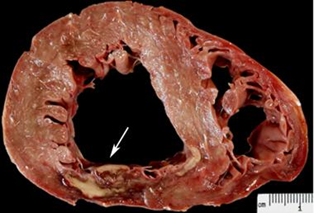

За макроскопічного дослідження міокарду помітна ділянка блідо-сірого кольору, яка відмежована смужкою червонуватого кольору. Діагностуйте патологію у ділянці із блідо-сірим забарвленням (А-В) та у ділянці червонуватого кольору периферійної зони (1-3).

А - інфаркт; Б – запалення; В - дистрофія;

1 - геморагічний вінчик; 2 - перифокальне геморагічне запалення; 3 - гіперемія.